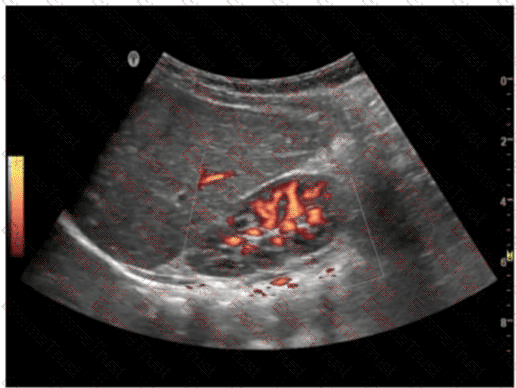

What causes color flash artifact?

Options:

A.

Aliasing

B.

Tissue motion

C.

High velocity blood flow

D.

Strong reflector